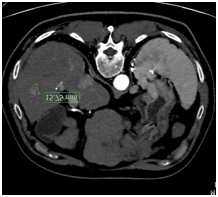

- 시술 전에 CT나 MRI영상을 촬영하여 시술 할병변의 개수와 크기를 확인

CT 또는 MRI로 병변 확인 초음파로 병변 확인